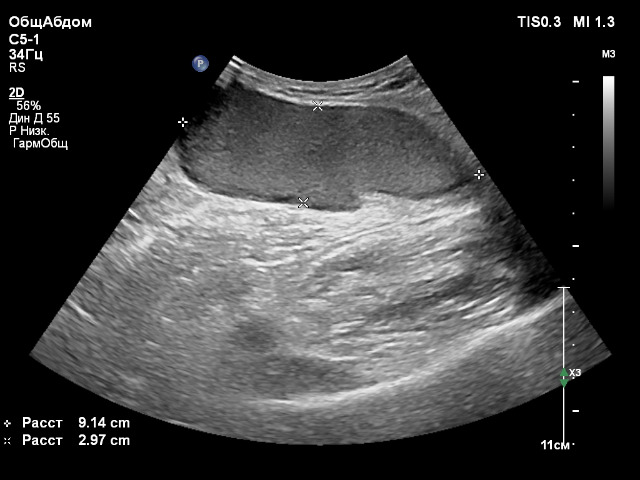

Мужчина, 61 год, пришел с "шишкой" в ягодице. Ощущает ее достаточно давно, говорит, что, возможно, появилась после инъекции. Расположена в ПЖК, четкие выраженно неровные контуры, дает "отроги" в виде пальцев, с такими же четкими контурами, в окружающий жир. Образование полностью аваскулярное, гипоэхогенное за исключением гиперэхогенного участка у одного из краев, ок. 30х15 мм, с нечеткими контурами, неправильной формы, тоже сравнительно однородного и аваскулярного. Посоветуйте, что может быть?

Наиболее вероятно- жидкостное образование ( абсцесс?). Отправляйте с описательной частью к хирургам.